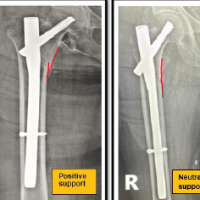

Out of the 2000 pregnancies, there were 1970 live births, with an overall incidence of CTEV at 0.355/100 live births. The median gestational age at the time of US was 19.64 weeks. Fetal anomaly scanning identified CTEV in 12 fetuses pre-natally. (Figure 1 & 2) Upon a review scan after 6 weeks, 2 patients were informed that the initial diagnosis was a misinterpretation, and the fetuses were normal. At birth, 7 cases were confirmed to have structural (bilateral) CTEV, while 3 cases were found to be positional deformities. (Table 1) During the study period, 10 feet were affected by clubfoot, with 3 cases being bilateral (6 feet) (Figure 3) and 4 cases being unilateral (4 feet). Among the neonates, 1039 (52.74%) were male and 931 (47.26%) were female. Post-delivery, all affected feet (10 out of 10) were treated using the Ponseti technique (Figure 4), and no additional open surgeries (posterior or posteromedial release) were performed on any of the patients. With a prevalence of 0.355, out of every 100 live-born infants, approximately 0.355 infants are born with CTEV. This means that in a population of 1,000 live births, approximately 3.55 infants would be expected to have CTEV. The PPV of the screening is 58.33%, meaning that when the test indicates a fetus has CTEV, there is a 58.33% chance that the fetus actually has a structural deformity that will require treatment using the Ponseti method. This indicates that about half of the positive diagnoses made by the US are confirmed as true positives upon further examination. The NPV of the test is 100%, indicating that when the screening test shows no signs of CTEV, it is certain that the fetus does not have the deformity. This high NPV demonstrates the test’s reliability in ruling out CTEV, ensuring no cases are missed. The sensitivity of the test is 100%, which measures the test’s ability to correctly identify all fetuses with CTEV. A sensitivity of 100% means that the screening test detected every case of CTEV, with no false negatives. This ensures that all affected fetuses are identified early. The specificity of the test is 99.75%, which indicates the test’s effectiveness in correctly identifying fetuses without CTEV. A specificity of 99.75% means that the test correctly identified 99.75% of the fetuses that did not have the deformity, with very few false positives.